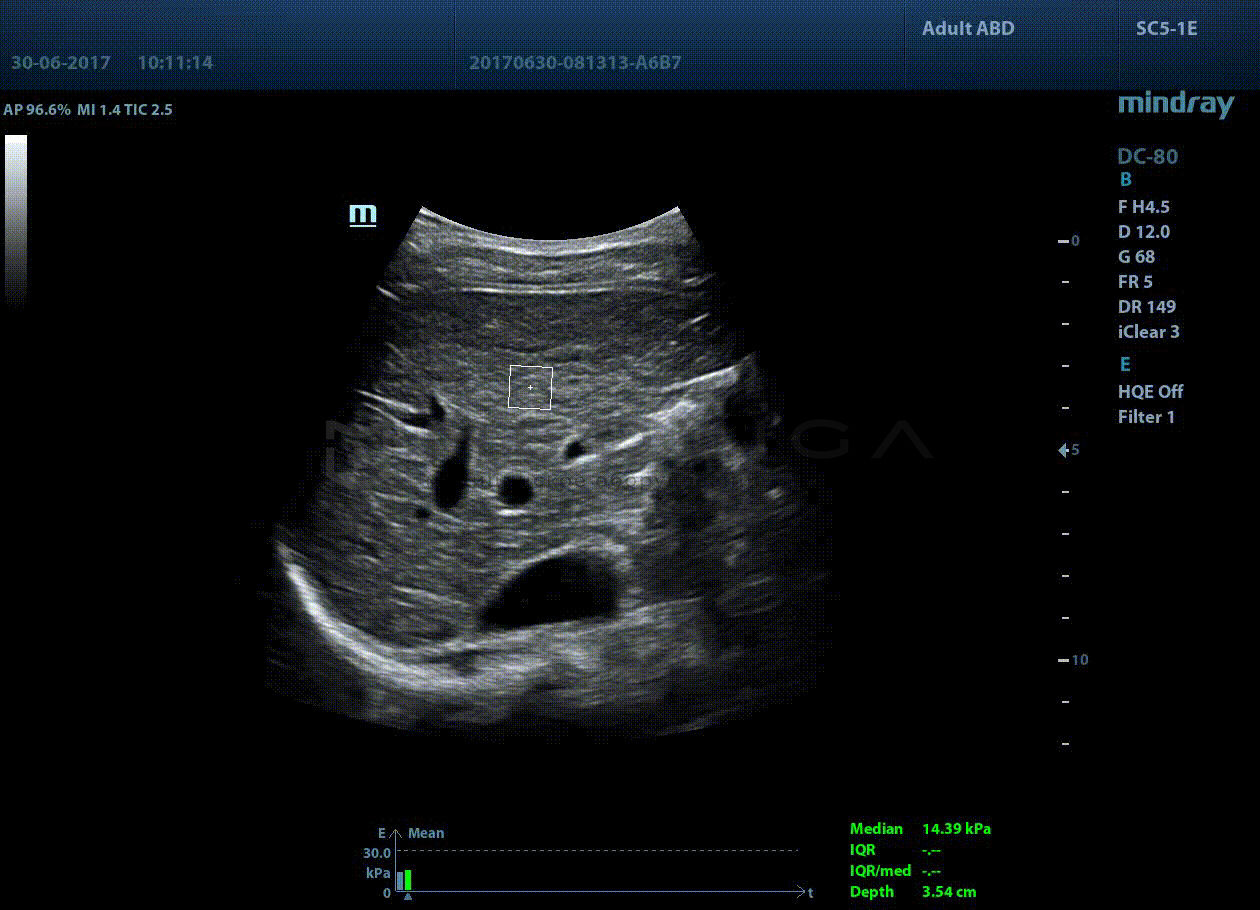

STQ (Sound Touch Quantification)

Sound Touch Quantification (STQ) позволяет быстро в режиме реального времени оценить жесткость ткани печени и определить стадию фиброза.